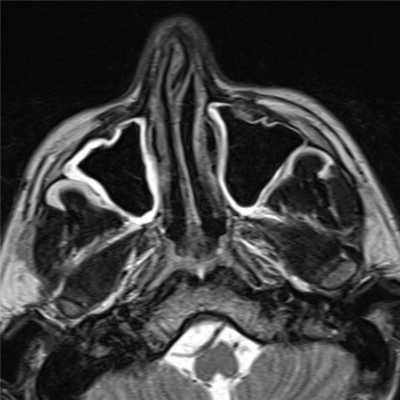

Больная Ж., 1957 года рождения, поступила в отделение ОГШ ФГБУ «РНИОИ» МЗ РФ 10.11.2017 г. с жалобами на затрудненное носовое дыхание через правую половину носа, кровотечения из правой половины носа. Из анамнеза: считает себя больной с ноября 2016 г., когда периодически отмечала кровотечения из правой половины носа. Обращалась к врачу по месту жительства, однако консервативное лечение, проводимое по месту жительства, осталось без эффекта. В марте 2017 г. по поводу зубной боли обратилась к стоматологу, где лечилась по поводу лакунарной кисты. В конце марта 2017 г. возникло кровотечение из правой половины носа. По месту жительства 10.04.2017 г. выполнялось прижигание сосудов слизистой оболочки полости носа справа. 10.05.2017 г. возобновилась кровоточивость с последующим носовым кровотечением. В ГБУ РО РОКБ 06.07.2017 г. выполнена операция: правосторонняя гайморотомия, этмоидотомия, удаление новообразования правой половины носа с использованием видеоэндоскопических технологий. Послеоперационный гистологический анализ № 57554-61 - кавернозная гемангиома. Больная была выписана в удовлетворительном состоянии с восстановленным носовым дыханием, кровотечение из правой половины носа прекратились. Через 1 неделю возобновились носовые кровотечения из правой половины носа, была направлена в ЛОР-отделение ГБУ РОКБ, где 18.08.2017 г. выполнена операция - правосторонняя гайморотомия комбинированным доступом (ревизия по Дэнкеру) с использованием видеоэндоскопических технологий, обезболивание общее. Послеоперационный гистологический анализ № 70827-30 от 25.08.2017 г. (ИГХ) меланома. Наблюдалась по месту жительства. Однако носовые кровотечения не прекратились, что побудило больную обратиться в ФГБУ «РНИОИ» МЗ РФ, где были пересмотрены гистологические препараты. Выполнены СРКТ околоносовых пазух и МРТ сосудов головного мозга. При осмотре специалиста в профильном кабинете клинико-диагностического отделения ФГБУ «РНИОИ» МЗ РФ: лимфатические узлы шеи не пальпируются. Лицо асимметричное за счет распространения опухоли в мягкие ткани правой щеки. Пальпаторно - костные края орбиты не изменены. При орофарингоскопии - открывание полости рта в полном объеме. При передней риноскопии - в общем носовом ходе справа гнойно-геморрагические корки, опухоль не определяется при осмотре. СРКТ от 27.10.2017 г. - опухоль правой верхнечелюстной пазухи 3,8х3,9х3,3 см с разрушением ее передней, задней стенок, распространением в мягкие ткани щеки и правый общий носовой ход; легочная ткань без очагов; патологических объемных образований в брюшной полости и полости малого таза не выявлено (рис. 3).